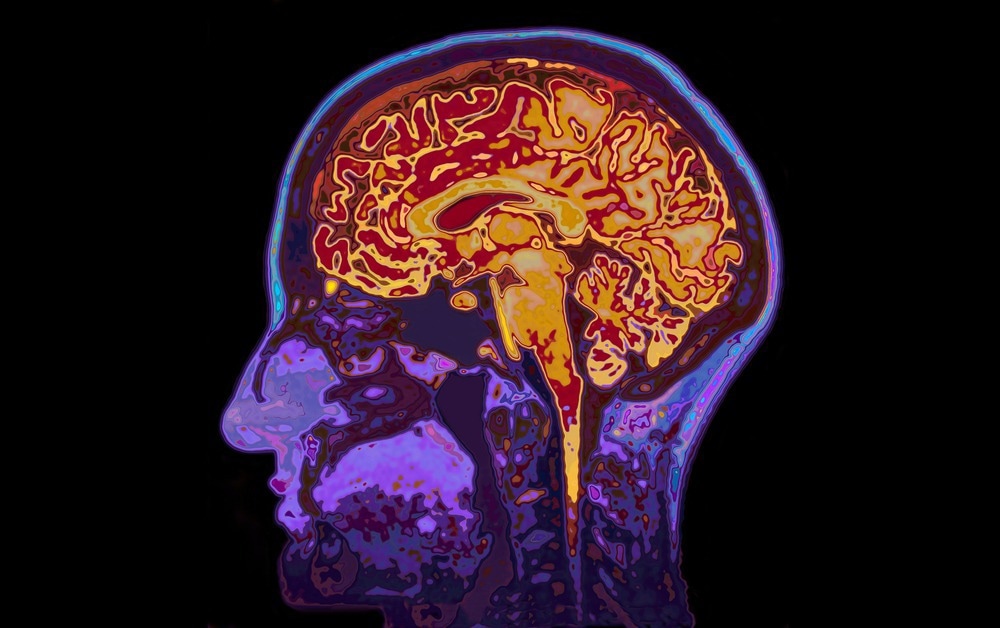

Molecular imaging is a form of molecular photography where we take snapshots of the molecules on highly complex surfaces, such as tissue sections or biopsies of cancer patients, solar cells, or even leaves with microbes growing on them, and we try to visualize them.

Molecular imaging produces a map or a photograph of the spatial location of the molecules combined with the identity of the molecules themselves.

Molecular imaging is entering digital pathology, a pathologist looking at digital images rather than through a microscope. As molecular imaging using mass spectrometers generates digital images, they can be shared easily with the pathologist.

They can be layered on top of the optical images that they already have. Now, the pathologist can augment how they look at the problem with molecular information. One example is detecting tumor cells in biopsy tissue. We can look at tissue sections from cartilage from damaged knees to understand the healing process and design new drugs.